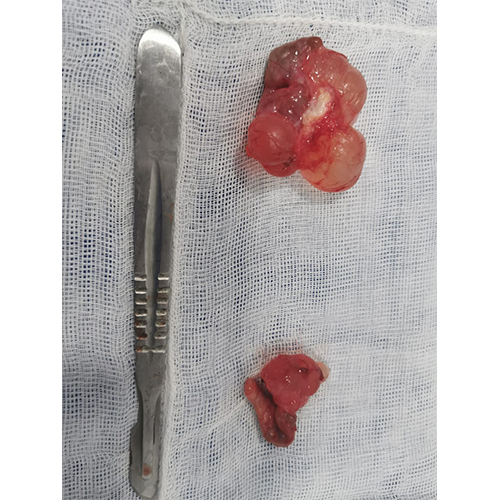

Atención y tratamiento a fragmentación, pulverizacion o extracción de cálculos o litiasis en la vejiga.

Atención y tratamiento a fragmentación, pulverizacion o extracción de cálculos o litiasis en Riñones.